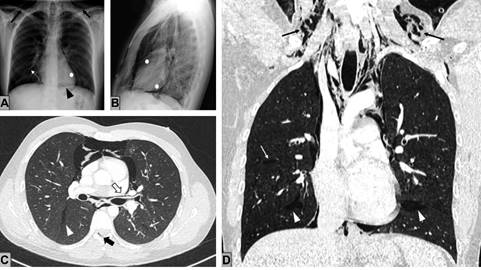

Se realiza una radiografía de tórax y se identifican signos de neumomediastino y enfisema subcutáneo cervical bilateral (Figura 1A y B). Se completa el estudio con una tomografía computarizada (TC) torácica, lo que confirma la presencia de neumomediastino con extensión a los planos cervicales profundos disecando los compartimentos mediastínicos (Figura 1C y D).

Figura 1: A) Radiografía de tórax posteroanterior. B) Lateral que muestra una radiolucencia lineal que dibuja el contorno mediastínico y cardiaco (asteriscos blancos), con el signo del diafragma continuo (punta de flecha negra), compatible con neumomediastino. Asocia focos de enfisema intersticial (flecha blanca) y enfisema subcutáneo cervical (flechas negras). C) Cortes axiales. D) Coronales de tomografía computarizada torácica sin contraste intravenoso que reflejan focos de enfisema intersticial y bandas aéreas lineales que disecan las vainas broncovasculares desde los bronquios distales hacia los hilios pulmonares (flecha hueca negra). El aire se extiende a mediastino, cisuras pleurales (puntas de flecha blancas), canal epidural (flecha gruesa negra) y planos musculares y tejido celular subcutáneo cervical. No hay defectos murales traqueobronquiales ni esofágicos.

El aire ectópico se extiende desde el intersticio pulmonar hasta la región hiliar, lo que conforma múltiples colecciones en áreas peribronquiales de morfología lineal (efecto Macklin). También se identifica contenido aéreo en cisuras pleurales y en espacio epidural (neumorraquis).